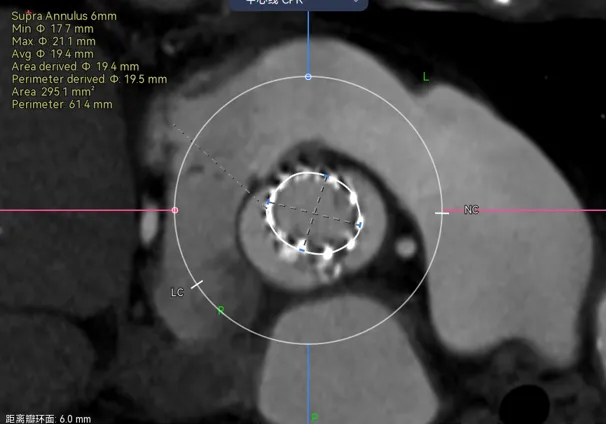

病例3 - 瓣上6-9mm的地方偏前交界缘的地方有一块钙化,如果是没有经验的可以能会这么画。

那就错了,需要先评估钙化重不重,对瓣膜有没有可能推挤,这里有个小诀窍,一般在瓣叶中间的钙化是可以推开的,除非他连接了基底部,而在交界区的钙化往往对瓣膜推挤作用和很强,做预估时要避开钙化的限制,如下图

结合下图术后CT可以看到,我对瓣膜位置的预判基本正确,钙化与升主的限制共同把瓣膜推向小弯侧,这时候可以看到瓣膜距离冠脉开口非常之近,如果再贴近一点,瓣膜植入再高一点,裙边或者吊桥可能会有冠脉阻挡风险。所以像这种单边钙化的冠脉风险也是需要看看的。